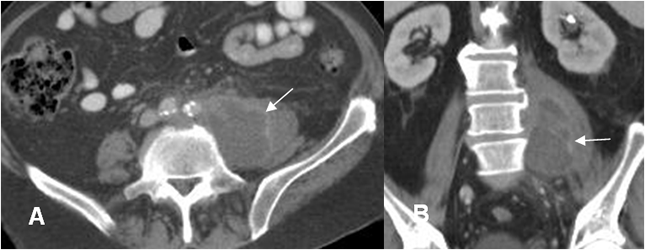

Fig 147 A. Absceso psoas.

A: TAC axial y B: TAC reconstrucción coronal. Colección en el psoas izquierdo, cuyos bordes captan el contraste, por absceso.